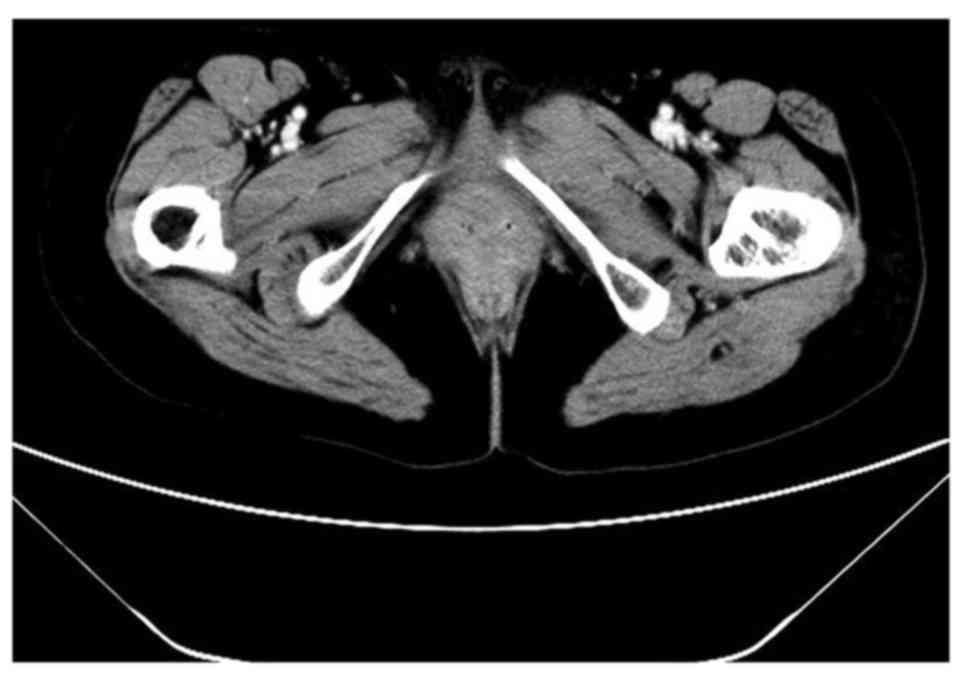

Following 2 cycles of chemotherapy, CT scans of the pelvis, abdomen and thorax were negative. Following the 6 cycles of chemotherapy, a CT scan (Fig. 6) and whole-body bone imaging (Fig. 7) revealed evidence of thoracic vertebral body metastasis. However, the abdomen and pelvis were negative for NHL. The patient received palliative radiation (36 Gy in 20 fractions) for the vertebral body metastasis. At time of publication, the patient was reviewed every three months and no recurrence or other metastasis had been observed.